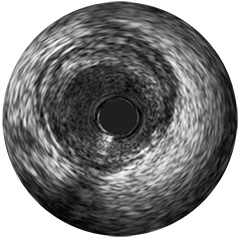

Abbildung 2